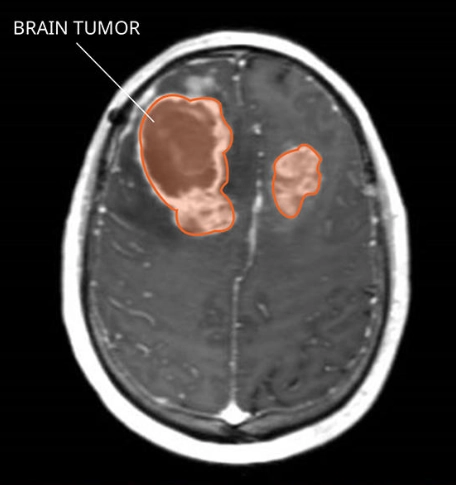

Di căn nhu mô não (Parenchymal metastases)